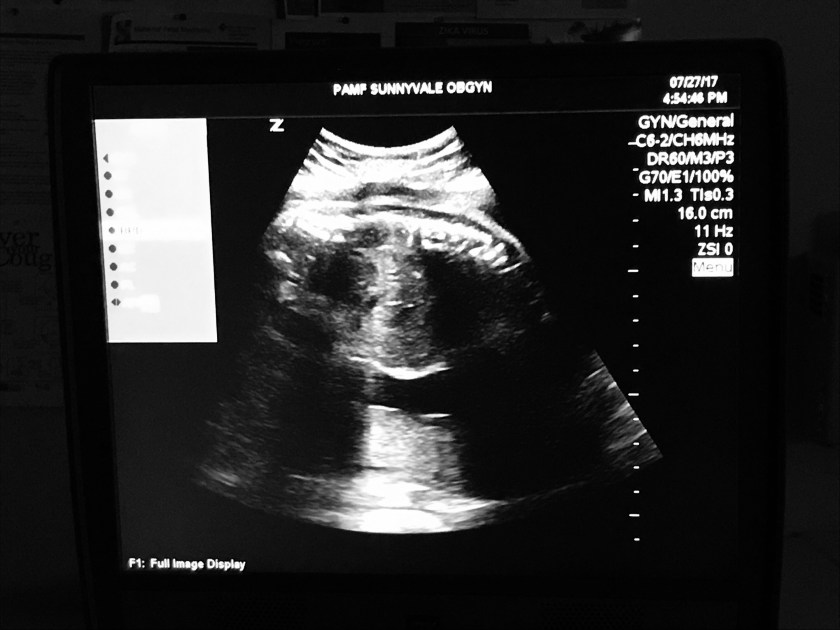

We saw a great clear view of baby’s spine.

We also saw baby’s head clearly. Our baby is measuring about 28 days which is bigger than our due date measurement of 26 weeks. This may be due to genetics with Matt having been a big baby.